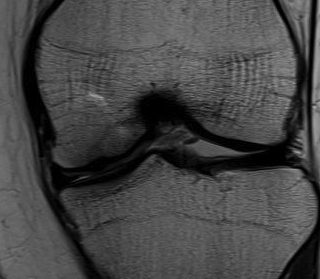

MRI

Plan

Probably unstable